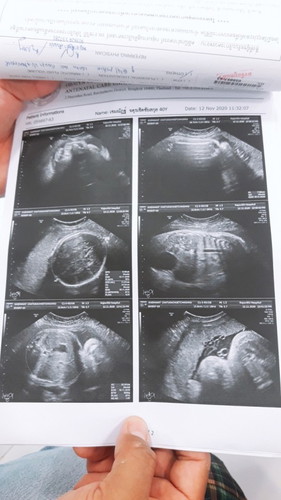

วันนี้คุณแม่มาตรวจครรภ์ตามหมอนัด 37+3 แต่ความดันไม่ปกติค่ะ วัดอยู่ 3-4 รอบ ได้ 131-150 แต่มีอาการเท้าบวมมาเป็นอาทิตย์ ก็ไม่ได้เอ๊ะใจอะไร เพราะคิดว่าคงบวมเพราะใกล้คลอด อย่างที่แม่ๆหลายคนบอกว่าใกล้คลอดแล้วจะบวมๆหายๆ คุณหมอก็ซาวด์ดูลูกว่ากลับหัวพร้อมจะคลอดกรือยัง สรุปไม่กลับค่ะ นอนขวางเพราะตัวใหญ่หรือหนูนอนท่านี้สบายก้อไม่รู้นะ คุณหมอเป็นห่วงเลยให้คุณแม่แอดมิท รอดูอาการเลยค่ะ พรุ่งนี้มีลุ้นว่าจะได้ผ่าคลอดเลยหรือปาวน่ะ อยากเจอหน้าลูกแล้ว แต่ก็อดห่วงว่าครรภ์ยังไม่ครบสมบูรณ์ดีหรือปาวน่ะ #ท้องแรกคะ